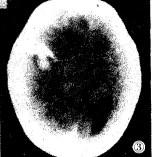

图1 脑内出血伴脑水肿。右顶叶脑实质内片状高密度影伴液血平面 。右大脑半球密度降低

图3 脑内出血、蛛网膜下腔 出血和硬膜下出血伴脑水肿。右颞叶脑实质内片状高密度影,右侧颅骨内板下呈镰状高密度 影,大脑后纵裂池密度增高,右大脑半球密度降低

硬膜下出血:8例,CT表现为沿颅骨内板下方呈“新月”形高密度影或带状混合密度影; 脑内出血:3例,CT表现为脑实质内片状、点状或团状密度增高影,近缘清楚而不光整,周 围可见低密度带环绕。

脑水肿:6例,CT表现为整个大脑半球或一侧大脑半球呈大片低密度影,脑室受压,中线结 构移位。